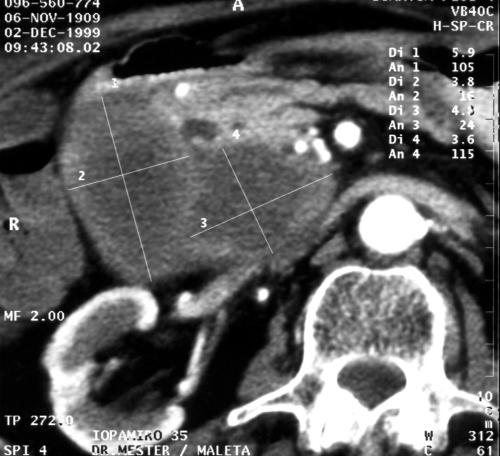

Figure 3. A 36 year old female with moderate epigastric pain. CT after contrast medium administration shows multiple cystic lesions in the head of the pancreas. Cystadenoma of the pancreas

Noncystic mucinous neoplasms have a central cystic mass, which is sometimes can be the only finding at CT examination.

Papillary-cystic tumors on CT appear as large non-homogeneous masses with a well-differentiated thick contour. This thick solid wall is enhanced after contrast administration. In the inner margin of the capsule, papillary nodules may be present. Calcification at the periphery of the lesion can be seen [15, 16].

Microcystic adenomas may display, according to the tissue composition, a conglomerate of small cysts. Macrocystic adenomas appear on plain scans as large multilocular cysts or conglomerates of cysts. The cysts are larger than 2 cm. After the administration of contrast material to both types of cystic adenomas, hypervascularized septas can be seen.